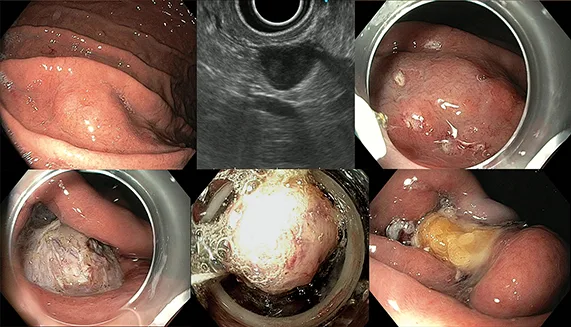

Figure 3 : Résection endoscopique d’une GIST gastrique hémorragique de 35 mm

Résection d’une tumeur sous-muqueuse hémorragique de 36 mm, sous-cardiale par technique STER (tunnélisation sous-muqueuse) sous eau en décubitus latéral gauche avec fermeture complète du défect musculaire limité et du défect muqueux par endoclips. La décision de résection endoscopique avait été prise en accord avec l’équipe chirurgicale du fait du caractère très protrusif de la lésion, stable sur le plan hémorragique sous IPP, de l’attache musculaire limitée à 15 mm, de la morbidité potentielle chirurgicale au niveau du cardia, et de l’accord de la patiente.